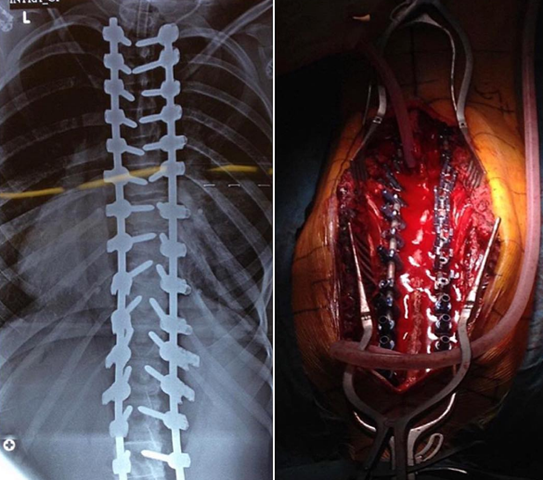

يطرح الطبيب المعالج خيار الجراحة عندما تكون درجة الانحناء أكثر من 45 درجة في مرحلة النمو او اكبر من 50 درجة في مرحلة ما بعد النمو

ويتم استخدام هذه الوسائل التعويضية من أجل تصحيح العمود الفقري وتثبيت الفقرات في الوضعية الصحيحة حتى يصبح بالإمكان إجراء عملية لحام للفقرات في كتلة عظمية واحدة.

المقطع التالي يبين طريقة العملية.